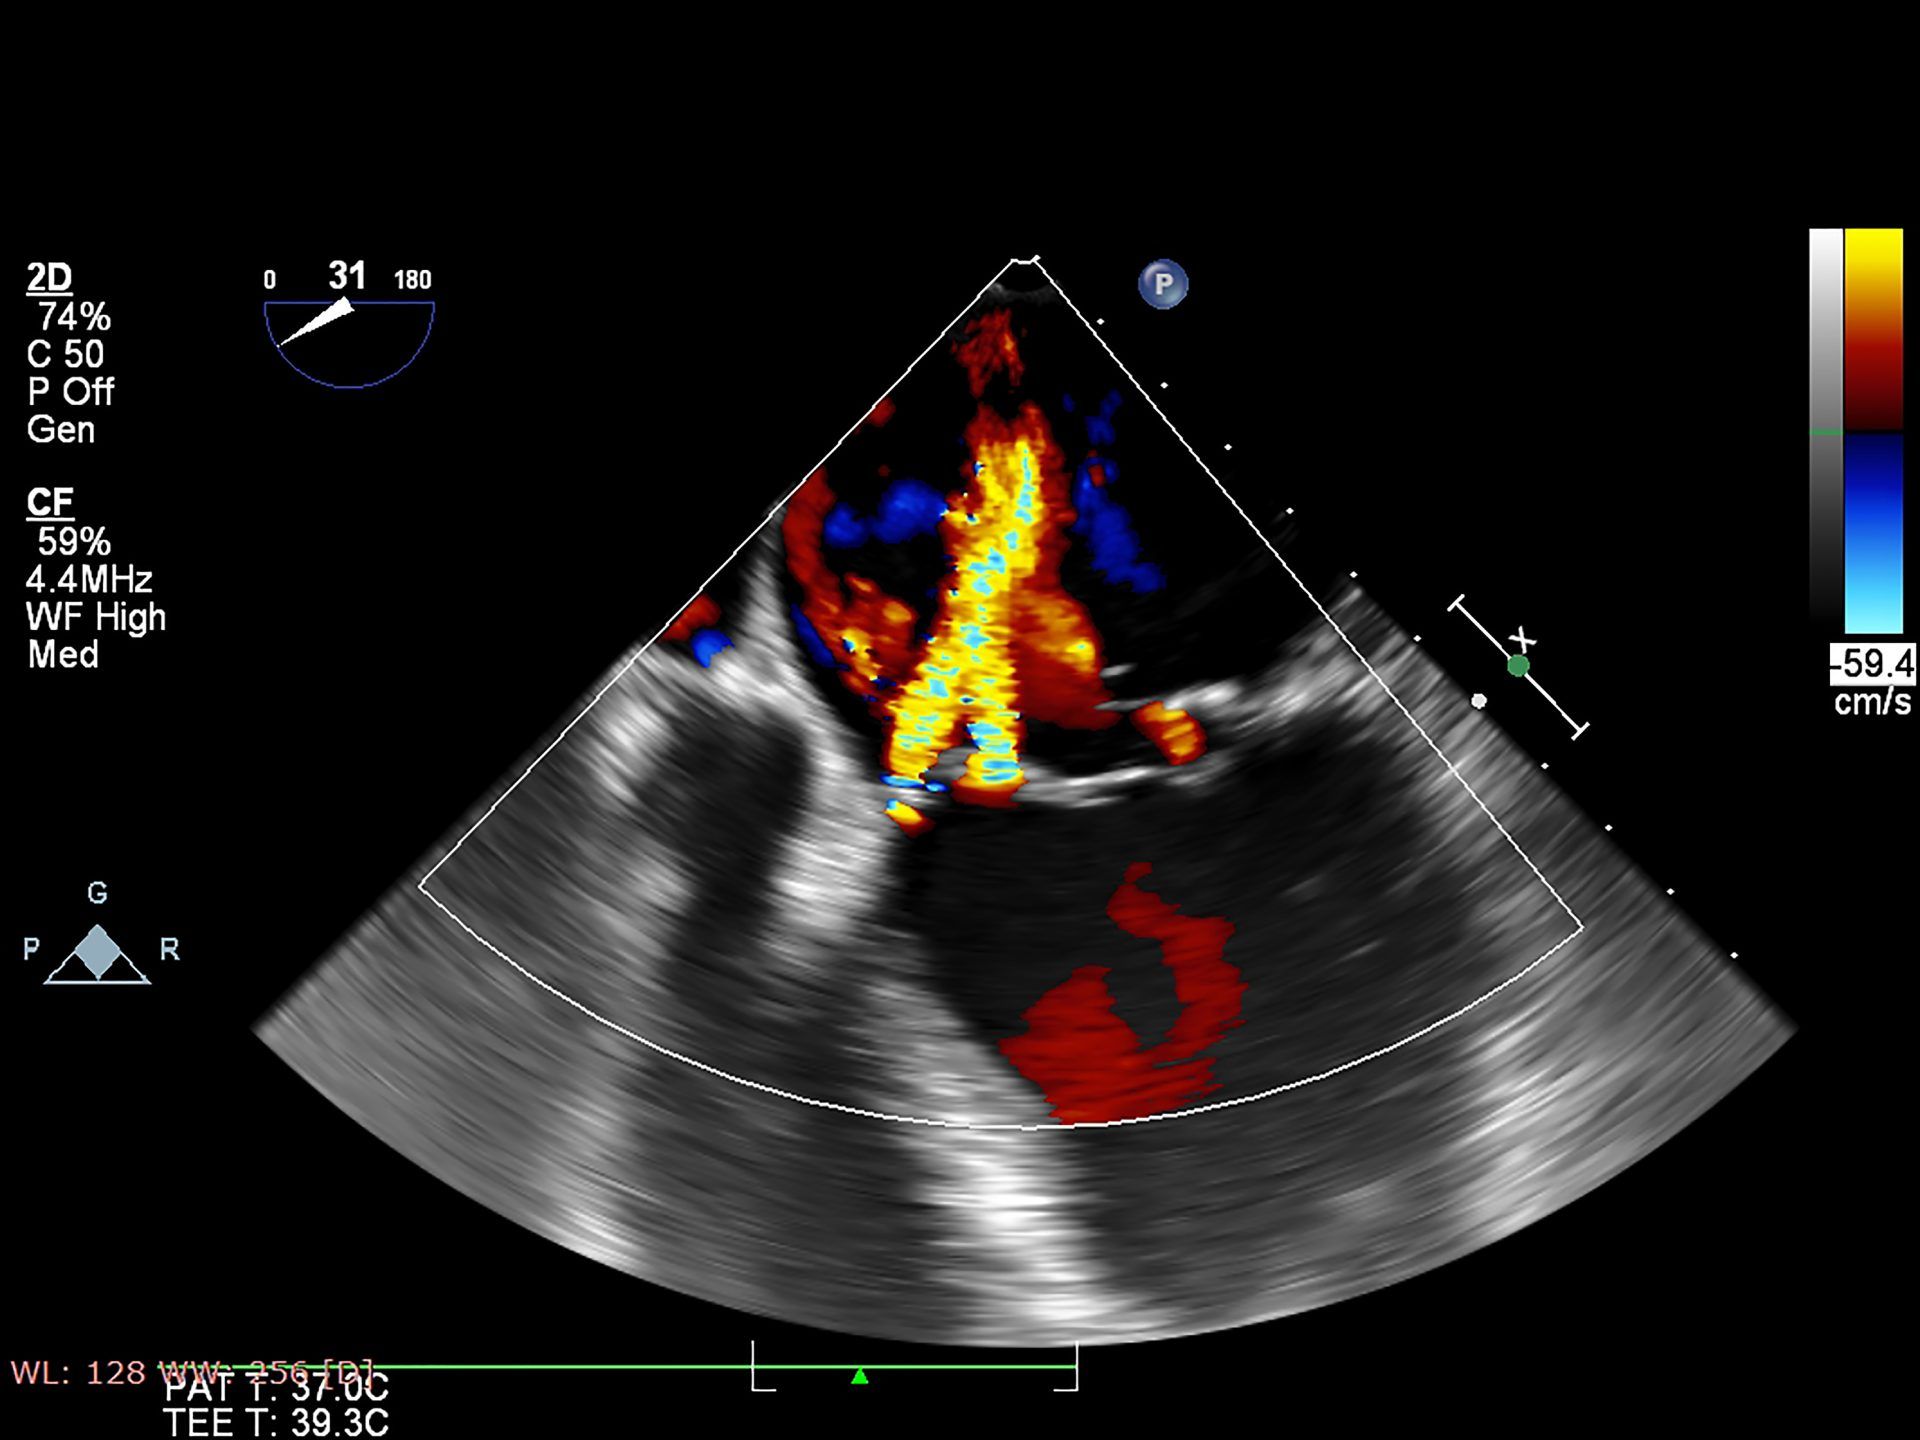

Аномалии легочных вен

Аномалии легочных вен 113 фото